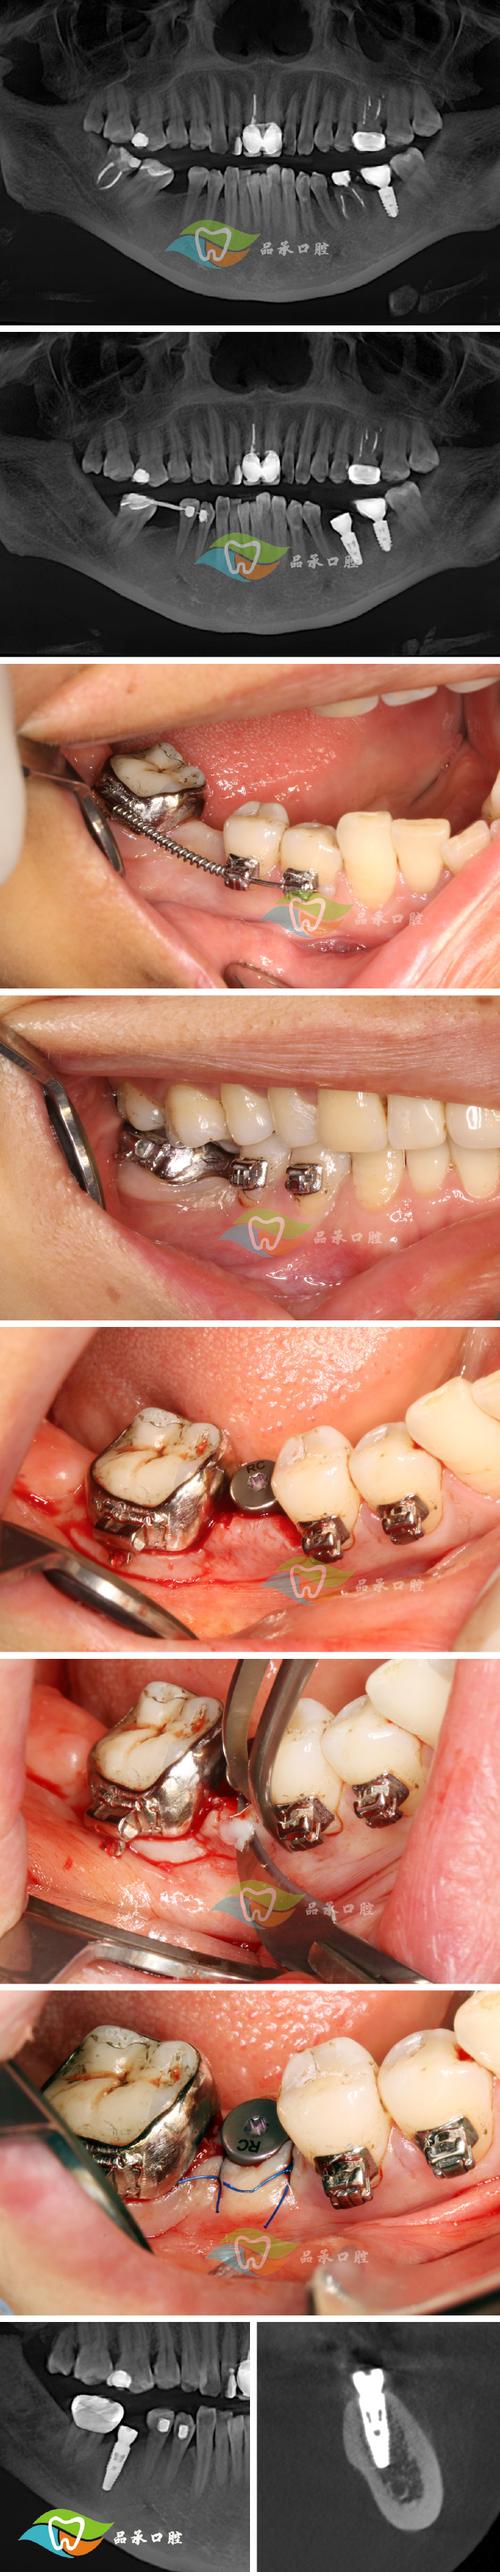

托槽或颊面管的影响:

如果问号钩是焊接在颊面管(后牙上的金属管)上,或者靠近托槽,其位置可能受到这些部件的限制,更容易压迫牙龈。